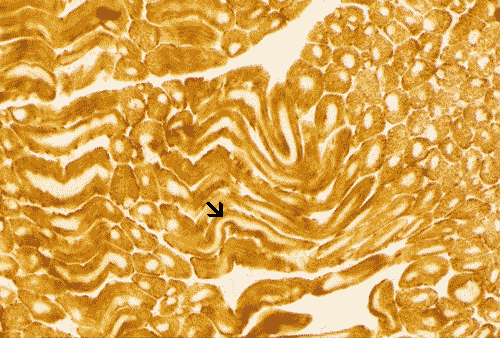

On COX reaction, a centrally located negatively reactive core is seen in practically every single muscle fiber. The cores extend along a long distance along muscle fibers as illustrated in the longitudinally cut sections (à). |